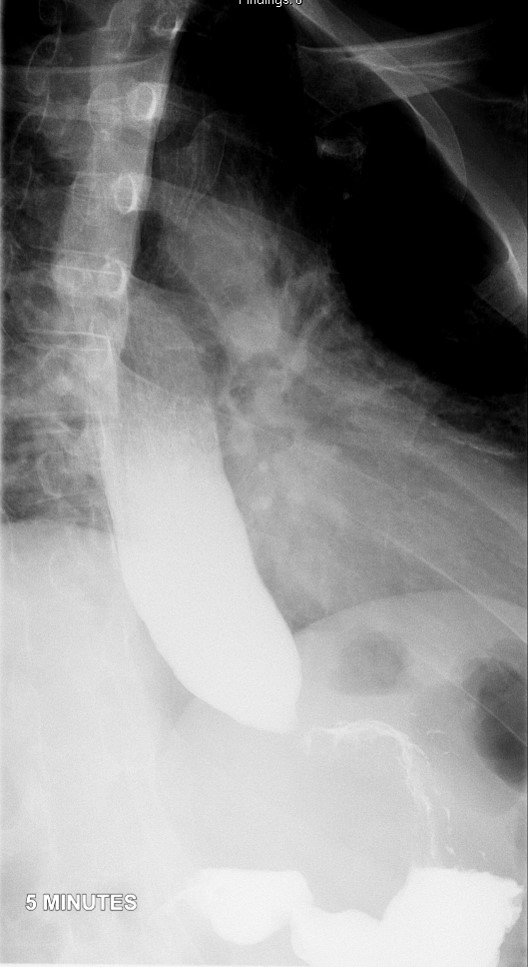

- Method:

- Place the patient in an upright LPO under the fluoroscope.

- Have the patient swallow the barium a period of 15 - 20 seconds.

- Obtain spot radiographs of the distal esophagus at 1, 2, and 5 minutes after ingestion of the barium

(key image 1)

(key image 2)

(key image 3).

- Ensure the distance between the patient and the fluoroscope is kept constant between all 3 radiographs.

- Images are obtained in the upright LPO projection.

- Films are obtained 1 minute, 2 minutes, and 5 minutes after contrast material administration.

- If contrast has emptied from the thoracic esophagus on the one minute image, the 2 minute and 5 minute images are not needed.